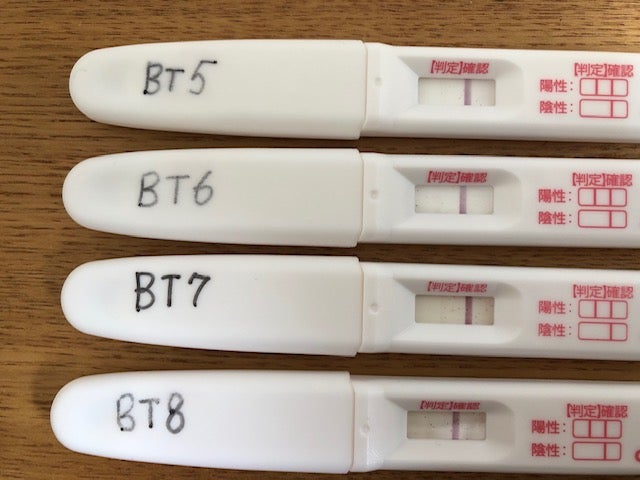

Jan 24, 19 · 妊娠検査薬で陽性反応が出てから、妊娠確定までにはいくつかのステップがあります。その一つが子宮内に「胎嚢(たいのう)」が確認されること。胎嚢って何? 胎嚢が確認できないのはどんなとき? 妊娠確定の第一歩「胎嚢」について、産婦人科医の新村朋美先生に詳しく伺いました。Feb , 17 · #妊娠検査薬陽性に関する一般一般の人気記事です。''おすすめ 妊娠検査薬 使いやすさ 感度 比較bt7''47歳 妊娠 義母に妊娠報告''d34 高温期16日目☆ついに、妊娠検査薬を‥‥''私が感じた妊娠超初期症状と生理前との違い''画像あり妊娠検査薬の陽性反応(デイビッド・クリアブNov 28, 15 · hcg注射を使用した場合は妊娠検査薬がhcg注射の成分に反応して、本当は妊娠していないにも関わらず陽性反応を出してしまう、偽陽性が出てしまうことがあります。hcg注射と妊娠検査薬についてのお話しです。

Jul 09, 04 · 今、ドキドキ高温期16日目のマンゴーです。 不育症で今まで妊娠2回・その2回とも流産を経験しています。 生理はいつもピタピタで来るので、昨日検査薬を試しましたが結果は陰性でした。 検査薬は1週間後からなんですけどね。 生理予定日前に薄茶色のおりものがあったので(着床出血Jul 29, 18 · ※検査薬の画像があるので不快な方は見ないでください。 先月、唾液排卵チェッカーがめっちゃシダってたにも関わらず生理が来てリセットしたので(シダってると妊娠してる説あり)、今月は尿タイプの排卵検査薬を使って妊娠検査薬と合わせ技でチェケラッチョしてみることにしましMay 10, · 妊娠検査薬での妊娠判定可能日を生理予定日一週間後としてるのには実は意味があります。 hcgホルモンが検出され陽性となったとしても、実際に病院で妊娠が成立したと確認できるのが6wあたりと言われているためです。